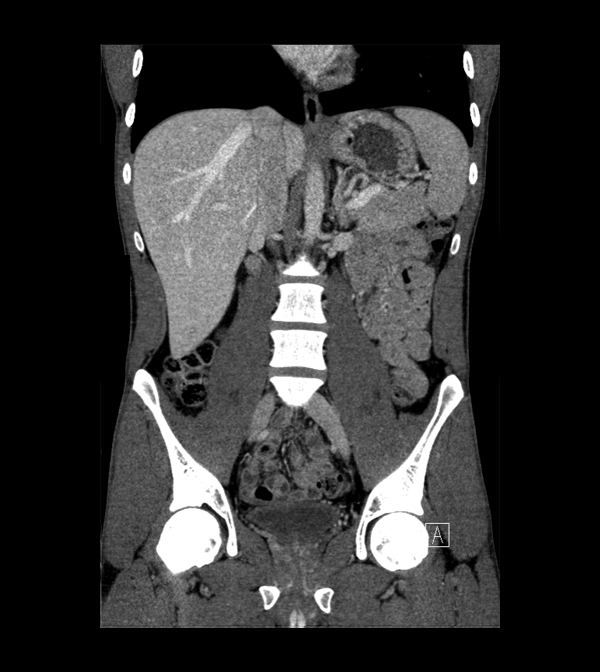

Body

Covers abdominal CT anatomy.